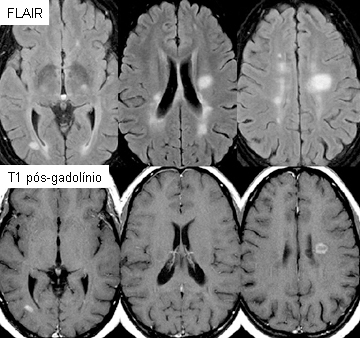

Deve ser realizada em magneto de alto campo (3 T é preferível, mas 1.5 T é aceitável), com contraste intravenoso baseado em gadolínio.[Figure caption and citation for the preceding image starts]: Imagens de ressonância nuclear magnética (RNM) axiais representativas usando recuperação da inversão atenuada por fluidos (FLAIR), mostrando lesões típicas observadas na esclerose múltipla (EM) nas regiões periventriculares. Cortes comparáveis usando o agente de contraste gadolínio ilustram quebra da barreira hematoencefálica/inflamação ativa em 2 das lesões. As lesões vistas no FLAIR que não captam contraste são, provavelmente, mais antigas, com uma combinação de gliose e nível baixo de inflamação crônica e degeneraçãoDo acervo do Dr. Lael A. Stone [Citation ends].

A recuperação de inversão atenuada por fluido (FLAIR) tridimensional (3D) sagital com aquisição de reconstruções multiplanares é recomendada. FLAIR axial ponderada por T2 deve ser obtida se essa sequência não estiver disponível.[3]

Quase todos os pacientes com esclerose múltipla (EM) terão uma RNM craniana anormal, mas a interpretação da RNM pode ser difícil. As imagens devem ser interpretadas por especialistas muito familiarizados com os achados típicos da EM na RNM.

Imagens FLAIR (recuperação de inversão atenuada por fluido) sagitais podem ajudar a distinguir entre lesões de EM e alterações inespecíficas da substância branca, como as observadas em associação com hipertensão, diabetes, idade >50, tabagismo, enxaqueca, colesterol alto e exposição a toxinas.[Figure caption and citation for the preceding image starts]: Imagens sagitais em recuperação de inversão atenuada por fluido (FLAIR) com lesões de esclerose múltipla (EM) típicas envolvem o corpo caloso, seja como lesões distintas ou como projeções semelhantes a dedos perpendiculares ao corpo caloso. Observe também o aumento dos ventrículos e a atrofia difusa da EM mais avançadaDo acervo do Dr. Lael A. Stone [Citation ends].

A RNM também é usada para avaliar a atividade da doença e monitorar a eficácia do tratamento.[3]

hiperintensidades na substância branca periventricular, as imagens mais sensíveis são as obtidas por recuperação da inversão atenuada por fluidos (FLAIR) no plano sagital